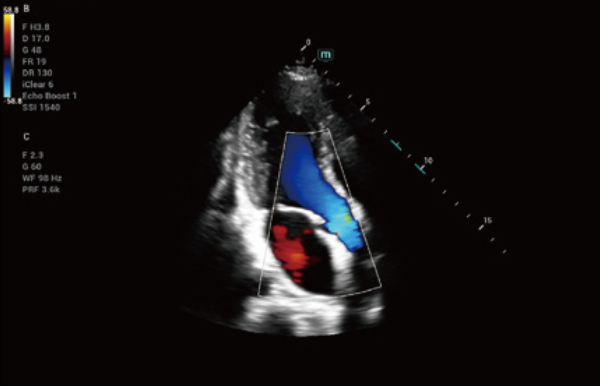

No matter your routine is in hospitals, clinics, or you are honing skills in General Imaging applications, women's health care or cardiovascular specialties, you will find highly powerful tools available on this series to keep you stay ahead.

Comprehensive Imaging Solutions Powered by ZST+

The ZST+ platform is an extraordinary innovation, representing an ultrasound evolution. Transforming ultrasound metrics from conventional beam-forming to channel data based processing. It overcomes the traditional trade-off limitation among spatial resolution, temporal resolution and tissue uniformity, delivering exceptional image quality for infinite imaging solutions with non-stop improvements.